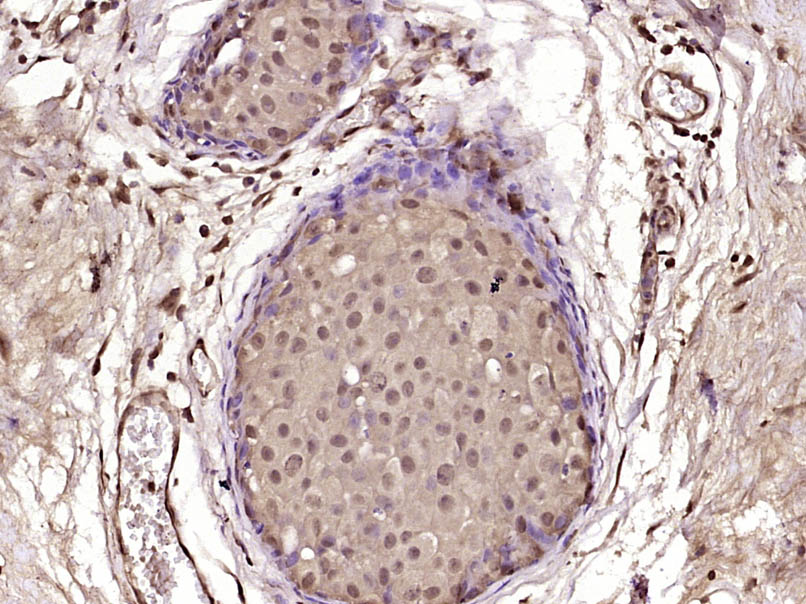

Paraformaldehyde-fixed, paraffin embedded (Human breast carcinoma); Antigen retrieval by boiling in sodium citrate buffer (pH6.0) for 15min; Block endogenous peroxidase by 3% hydrogen peroxide for 20 minutes; Blocking buffer (normal goat serum) at 37°C for 30min; Antibody incubation with (CECR2) Polyclonal Antibody, Unconjugated (bs-13824R) at 1:400 overnight at 4°C, followed by operating according to SP Kit(Rabbit) (sp-0023) instructionsand DAB staining.